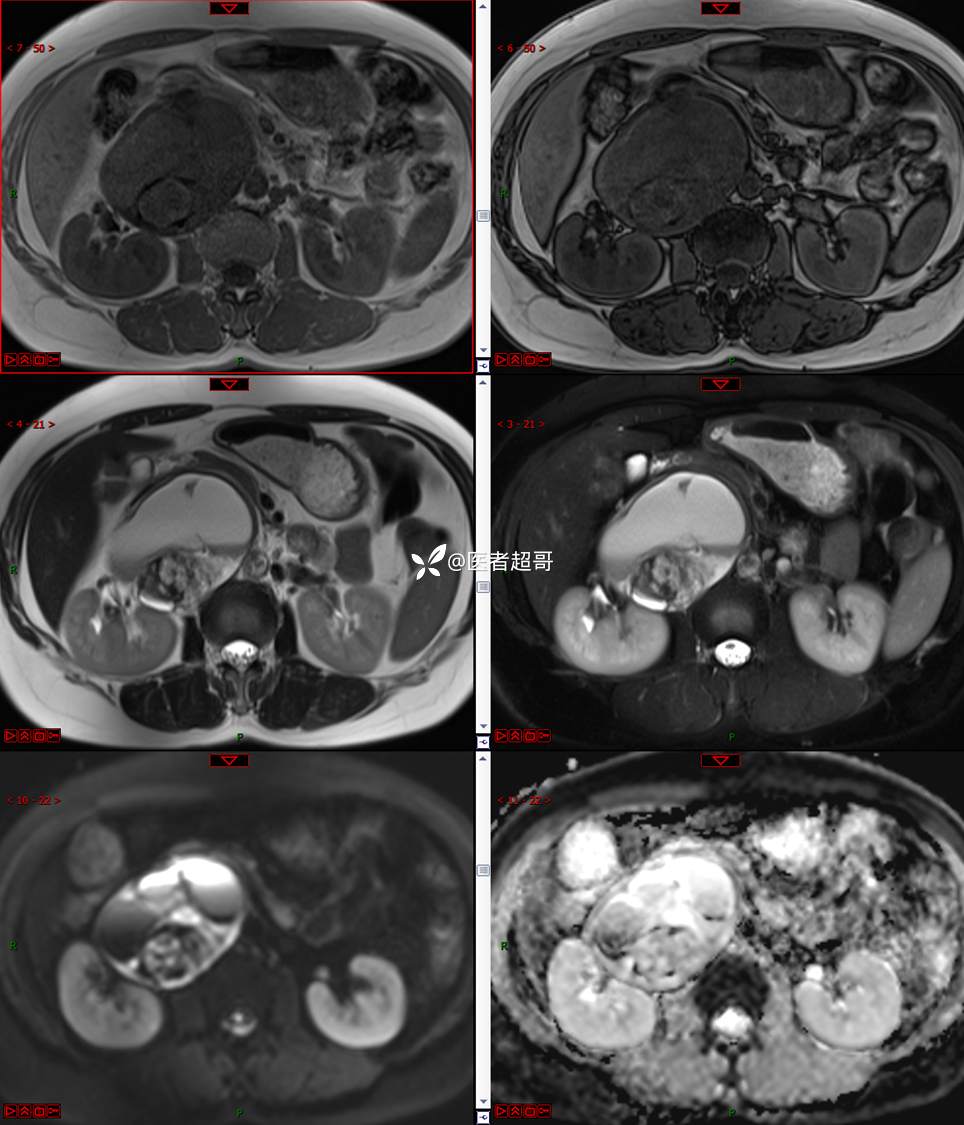

【影诊笔记671】定位有难度,究竟是腹腔内or腹膜后,请先定位,再定性!有结果~~~

hyy838 推荐女,52岁

主诉:查体发现腹部肿物1周。

现病史:患者1周前于我院查体发现右侧腹部肿物,无腹痛、腹泻、便血,无恶心、呕吐,患者为求进一步治疗,遂就诊于我院,门诊以“腹部肿物”收入院。患者自患病以来睡眠可,精神可,饮食可,小便无明显异常,体重无明显变化。

专科检查:腹部平坦,腹肌软,无压痛及反跳痛,无包块,肝脾无肿大,Murphy征阴性,腹部叩鼓,肝脾双肾无叩痛,移动性浊音阴性,肠鸣音正常。我院 肝胆胰脾肾彩超提示:脂肪肝、腹腔内囊实性团块,建议进一步检查。